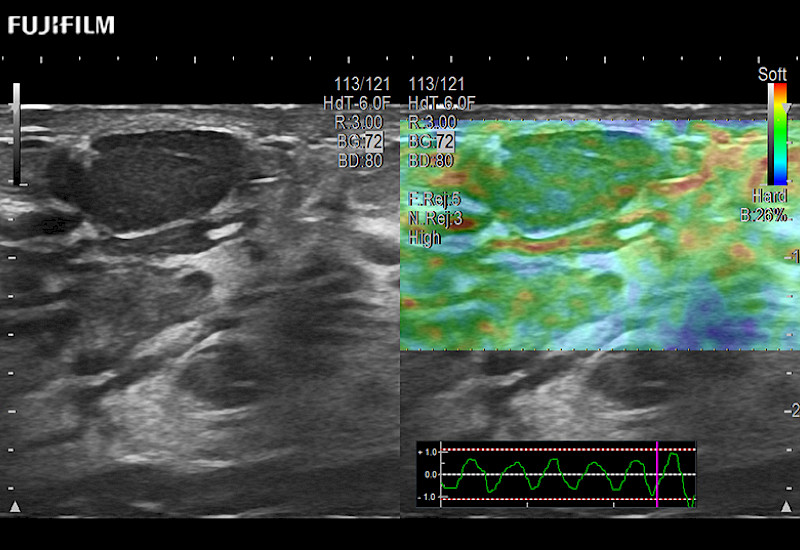

For precise surgical oncology ultrasound imaging, Fujifilm Healthcare offers premium level solutions that include:

Extraordinary high-resolution digital imaging

Multi-Parametric imaging modalities

Our dedication to Surgical Oncology allows us to offer superior image quality, outstanding system reliability and intuitive use of cutting edge technology.

ARIETTA 750 for Surgical Oncology

The ARIETTA 750 incorporates all of the proven technologies and functions that medical professionals have come to expect from Fujifilm Healthcare.

ARIETTA 750 is the definitive diagnostic ultrasound solution for any clinical setting - Private Office, Imaging Center, or Hospital. The ARIETTA platform provides the ultimate in clinical performance with its state-of-the-art features and large user-friendly display.

ARIETTA 650 DI for Surgical Oncology

The ARIETTA 650 DI combines trusted Fujifilm Healthcare technologies and features tailored for surgical oncology.

Designed to meet the demands of surgeons, the ARIETTA 650 DI offers precise guidance. Its advanced capabilities and large, intuitive display offer accurate and efficient care in operating rooms and specialized surgical settings.